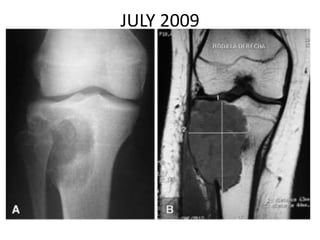

JULY 2009

SEPT 2009